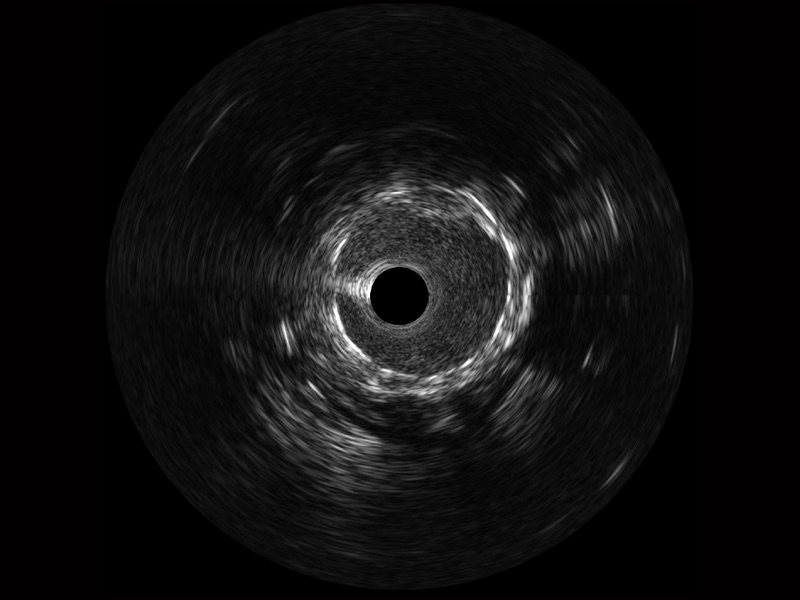

• 哈哈体育官网宽频IVUS图像

• 传统IVUS图像

对比传统IVUS导管成像,哈哈体育官网宽频IVUS图像的近场支架梁显影更细腻,远场中膜外血管仍清晰可辨,兼顾远中近,兼顾分辨力与穿透深度